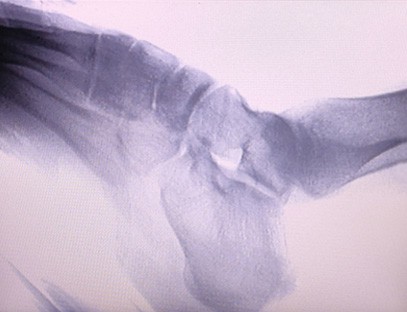

Prenosni rentgenski aparatje zelo varen prenosni instrument z nizko dozo sevanja, ki lahko pridobi visokokakovostne slike in hkrati zmanjša izpostavljenost sevanju. Kompenzira pomanjkljivosti velike bolnišnične opreme in ga je mogoče kadar koli premikati in prenašati. Posebej primerno za enote in posameznike z nezadostnim proračunom in nizkimi zahtevami po slikah. Naš rentgenski aparat nove generacije je opremljen z 10-palčnim velikim zaslonom visoke ločljivosti, ki ima večji razpon vidnega kota in lahko popolnoma vidi skozi celotno dlan, vključno z zlomi, izpahi, artritisom in kostnimi tumorji. Lahko se poveže s filmskim tiskalnikom za tiskanje ortopedskih filmov, lahko pa se uporablja tudi za industrijsko proizvodnjo in testiranje. Ni potrebe po temnici, neposredna perspektiva, opazovanje v realnem času. Ta stroj ima slikovni sistem visoke ločljivosti, ki lahko zelo jasno zajame slike katere koli strukture kosti. Zagotoviti najboljšo opremo za testiranje rentgenskih žarkov in rešitve za proizvajalce medicinskih, hišnih, industrijskih in elektronskih izdelkov, inšpekcijske in vzdrževalne oddelke ter raziskovalne laboratorije.

Specializacija:Zasnovan za potrebe ortopedskih klinik, posebej primeren zaRentgensko slikanjeokončin, kot so roke, zapestja, komolci, ramena, kolena, gležnji itd.

Jasna slika:Napredna tehnologija digitalnega slikanja se uporablja za zagotavljanje visokokakovostnih rentgenskih slik, kar zdravnikom pomaga pri natančni diagnozi bolezni.